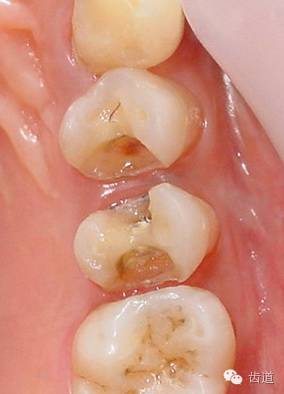

1、上頜前磨牙銀汞充填后食物嵌塞

2、去除銀汞充填物并作嵌體牙體預(yù)備

3、樹(shù)脂暫時(shí)嵌體覆蓋窩洞

4、瓷嵌體制作

5、瓷嵌體粘結(jié)